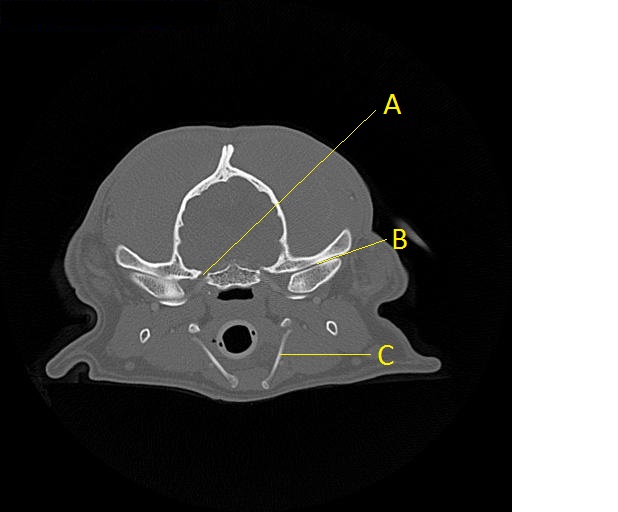

Q.  Identify the structures labeled below:

A.

A.  Foramen ovale

B.  Temporalmandibular joint

C.  Epihyoid